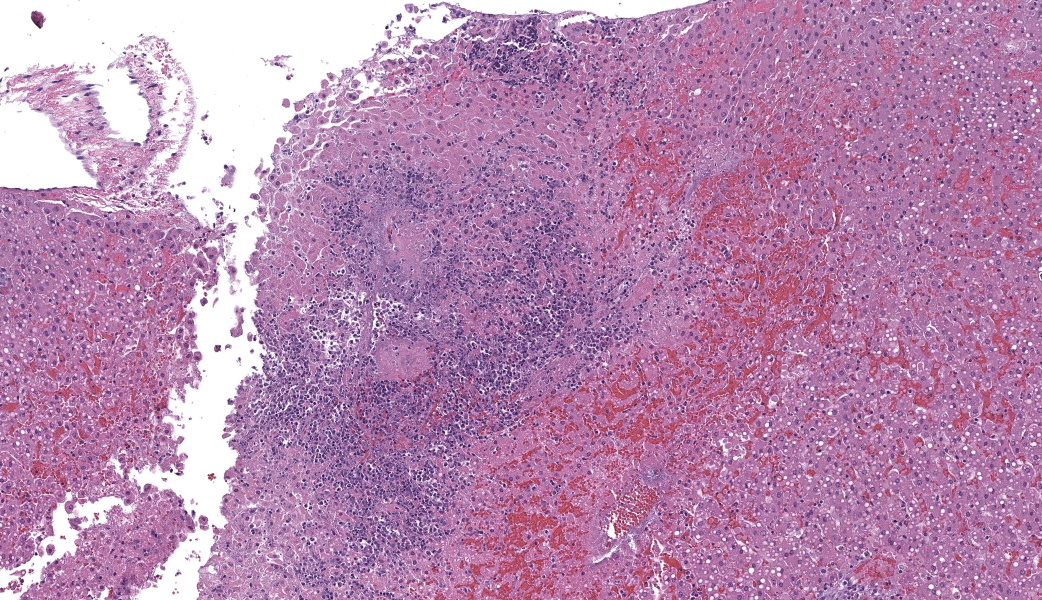

Microscopic Description:

Gallbladder and liver: The gallbladder and adjacent portal tracts are effaced by multifocal to coalescing areas of coagulative and lytic necrosis admixed with foci of suppurative inflammation. The gallbladder is transmurally severely expanded by numerous neutrophils, scattered lymphocytes and histiocytes, abundant polymerized fibrin, necrotic debris eosinophilic proteinaceous fluid (edema), extravasated red blood cells (hemorrhage), and mats of extracellular rod-shaped bacteria (bacilli). Multifocally, blood vessels in the gallbladder are distorted by endothelial and/or mural necrosis and innumerable bacilli. Some vessels are partially occluded by fibrin and bacterial thrombi. Remaining intact vessels are congested. There is marked loss of gallbladder epithelium characterized by hypereosinophilia and loss of nuclear detail (necrosis), occasionally seen sloughing into the lumen admixed with neutrophils, fibrin, and red blood cells. Throughout the liver, bile ducts and portal vasculature undergo similar changes of varying severity (Fig 2). Bacilli are located extracellularly within portal areas and within sinusoids or intracellularly within macrophages. There are moderate, acute, multifocal loss of hepatocellular detail admixed with areas of fragmented chromatin and karyolytic debris (coagulative and lytic necrosis). Remaining hepatocytes are mildly to moderately swollen by small to medium-sized, round, clear, cytoplasmic vacuoles.

- Gallbladder: Severe, acute, multifocal to coalescing, necrotizing and suppurative, transmural cholecystitis with hemorrhages, congestion, polymerized fibrin, edema, and intralesional bacilli

- Vasculature, gallbladder and liver: Marked, acute, multifocal endothelial necrosis with mural bacterial colonization, bacteremia, and fibrin thrombi

- Liver: Severe, acute, multifocal, necrotizing and suppurative cholangiohepatitis with multifocal hemorrhages, acute random hepatic necrosis, and intralesional bacilli

- Gallbladder: Cholecystitis, necrosuppurative, acute, diffuse, severe, with vasculitis and innumerable bacilli.

- Liver: Cholangiohepatitis, necrosuppurative, acute, multifocal to coalescing, severe, with portal vein thrombi, random hepatocellular necrosis, and innumerable bacilli.